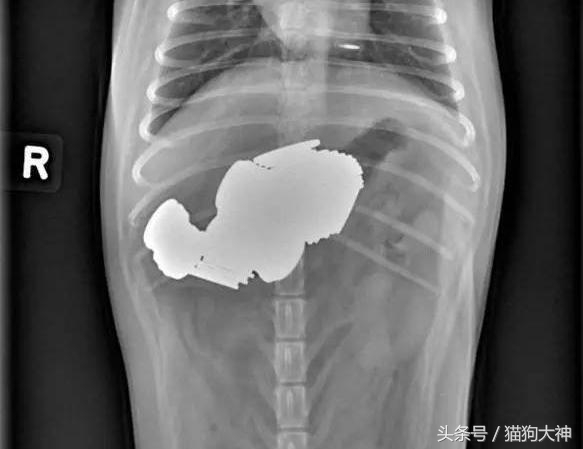

这只大丹犬曾经震惊过整个宠物医疗界。某天,主人发现狗狗精神不振,于是连忙送去了医院。

这是X光片的情况,狗狗的胃里塞满了不知道是什么的东西,反正消化不了并且堵住了肠胃。

手术结束后,医生将从狗狗胃里取出的43只袜子摆在了主人面前,主人简直惊呆,他没想到,家里丢失的那些袜子竟然全部被狗吞了。